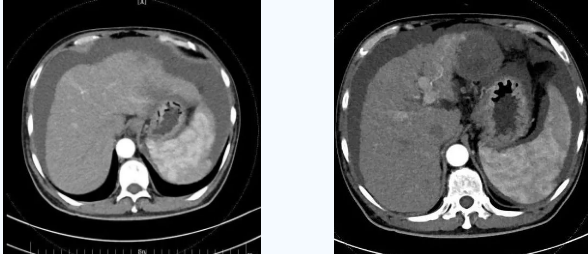

術(shù)后一個月秦先生來院復(fù)查,腹水已明顯較前減少,精神和飲食較術(shù)前明顯好轉(zhuǎn)。

韓國宏院長介紹,TIPS原理是采用特殊的介入治療器械,在X線透視導(dǎo)引下,經(jīng)頸靜脈入路,建立肝內(nèi)的位于肝靜脈及門靜脈主要分支之間的人工分流通道,并以金屬覆膜內(nèi)支架維持其永久性通暢,達(dá)到降低門脈高壓后減少腹水產(chǎn)生,控制和預(yù)防食道胃底靜脈曲張破裂出血的目的。